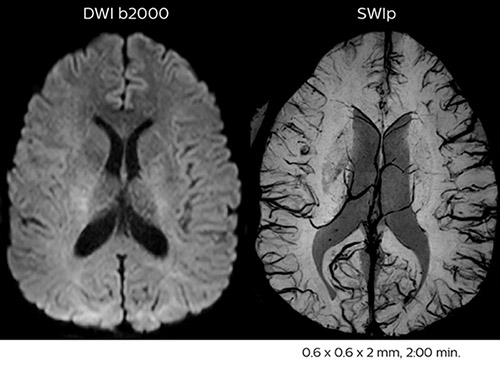

Using MultiBand SENSE allowed the staff to improve their diffusion quality. “Our diffusion sequence was already fast before, about 40 seconds. Now with Elition, it still lasts 40 seconds, but we improved the spatial resolution by 0.2 mm and use high b-values to be more sensitive to visualize changes related to acute stroke,” says Dr. Savatovsky. “We now also developed a high resolution DTI sequence (1.3 x 1.3 x 2 mm) that can be reformatted and takes 2 to 5 minutes depending on the coverage. We use it every time we have a doubt, or when we expect the diffusion to be abnormal but don’t see that on the fast sequence. We occasionally spot small ischemic infarctions that would not have been visible with the regular diffusion sequence.”

This is an example of acute ischemic stroke with distal occlusion of the right posterior cerebral artery. Note the improved visibility of the ischemic territory on the diffusion weighted image with high b-value. The 3D FLAIR shows a distal PCA occlusion. The fast SWIp depicts the thrombus on the isolated second echo image. The total scan time (including SmartBrain, preparations and a fast 3D T1w TSE Gd) is 8:00 minutes.

In this patient with acute right motor deficit and aphasia, the b2000 diffusion weighted image is normal. The SWIp image demonstrates more prominent veins in the right hemisphere, which could reflect increased deoxyhemoglobin contents. Fast ASL shows low CBF regions in the left frontal lobe. A follow-up ASL after one hour demonstrates high CBF values in the same area. The final diagnosis was migraine with aura.